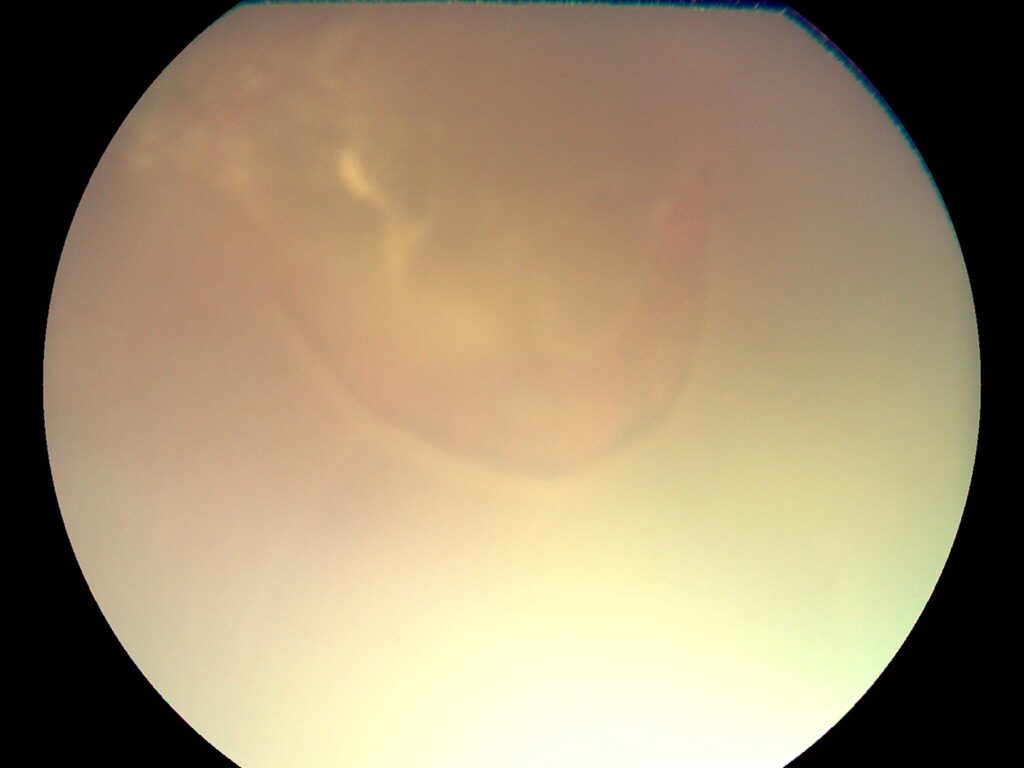

Optic disc neovascularization